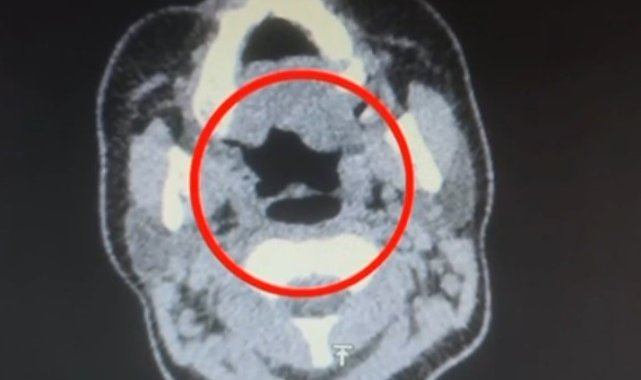

Kayseri'de uluslararası uyuşturucu madde ticareti yapan kuryenin midesinde 50 adet kapsül şeklinde 500 gram uyuşturucu madde ele geçirildi.Kayseri İl Emniyet Müdürlüğü Narkotik Suçlarla Mücadele Şube Müdürlüğü ekipleri, uluslararası uyuşturucu madde ticareti yapan kurye şahıslara yönelik operasyon düzenledi. Operasyonda A.R.'yi (27) gözaltına alan ekipler, şahsı hastane muayenesine götürdü. Şüphelinin yapılan iç beden muayenesinde, mide kısmında bulunduğu tespit edilen 50 adet kapsül şeklinde toplam 500 gram uyuşturucu madde ele geçirildi.'Uyuşturucu madde ticareti yapmak' suçundan gözaltına alınan şüpheli emniyete götürüldü.

Kayseri'de uluslararası uyuşturucu madde ticareti yapan kuryenin midesinde 50 adet kapsül şeklinde 500 gram uyuşturucu madde ele geçirildi.